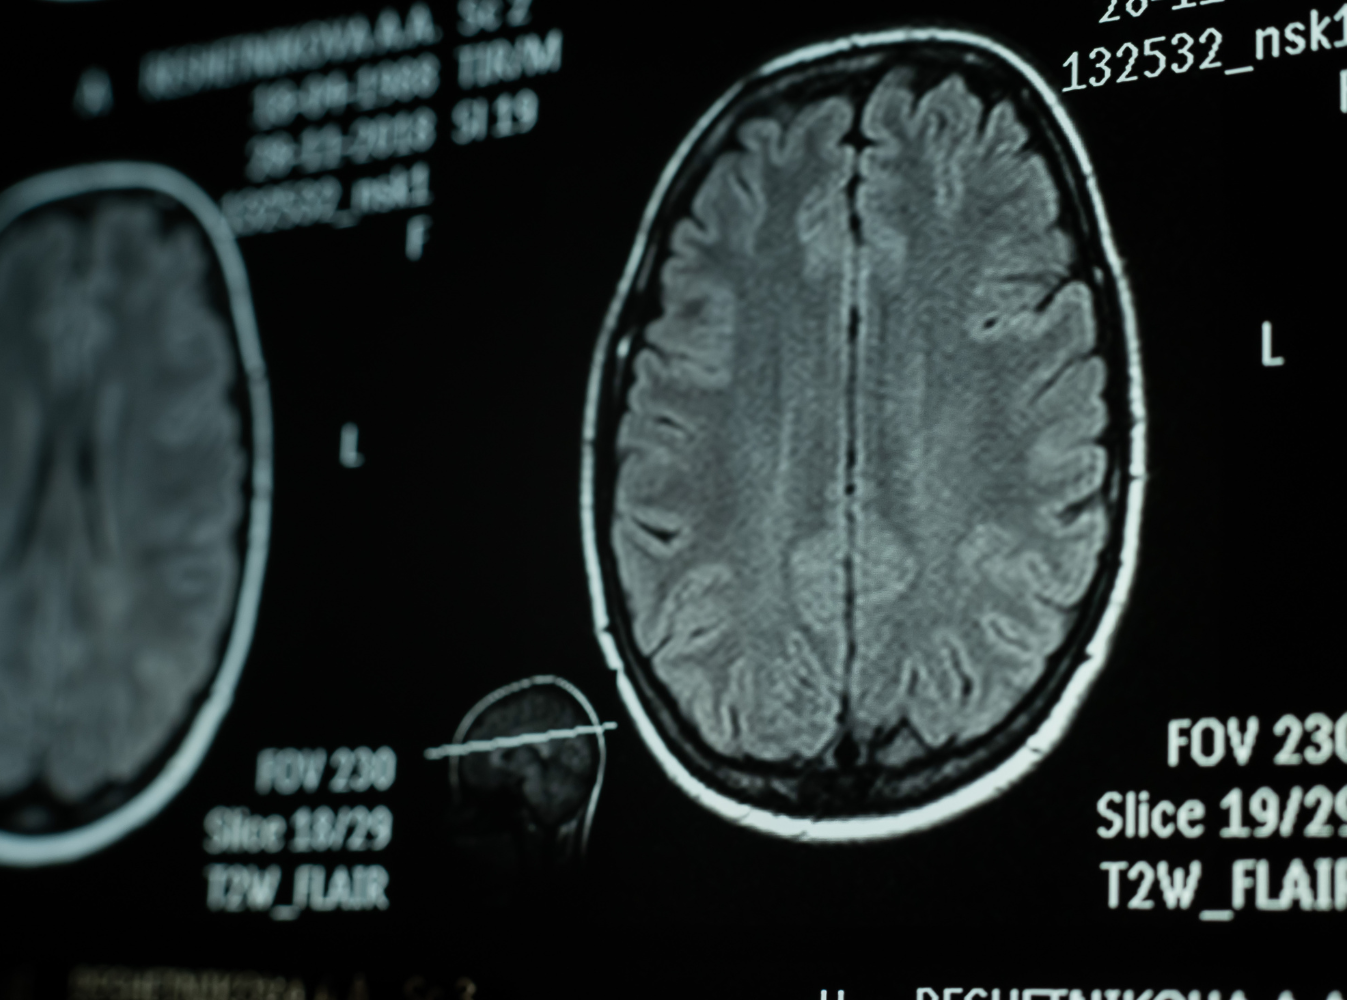

Medical professionals diagnose TBIs through observation or MRIs. A medical professional may use a system called the Glasgow Coma Scale to determine the level of consciousness and diagnose your injury. Common TBIs from automobile accidents include: